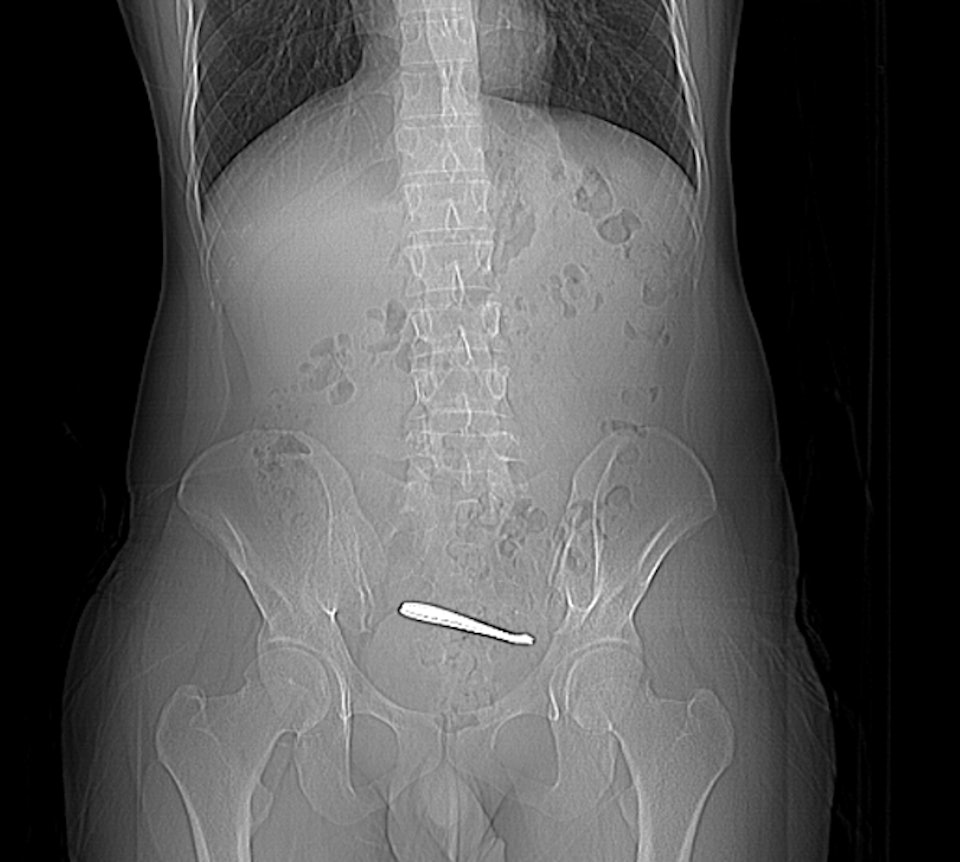

Kết quả chụp CT cho thấy dị vật nằm trong khoang chậu.

Sau khi ông Zhang nhập viện, ông đã được chụp CT và nội soi đại tràng, kết quả cho thấy hai chiếc thìa bị mắc kẹt ở đoạn cuối hồi tràng. Niêm mạc xung quanh bị loét, tiềm ẩn nguy cơ thủng ruột. Các dị vật dài khoảng 12 cm và nằm ở đoạn ruột non hẹp, khiến việc lấy ra khá khó khăn. Sau gần một giờ phẫu thuật, các bác sĩ đã lấy thành công cả hai chiếc thìa ra nguyên vẹn bằng nội soi.

Chiếc thìa dài khoảng 12 cm.